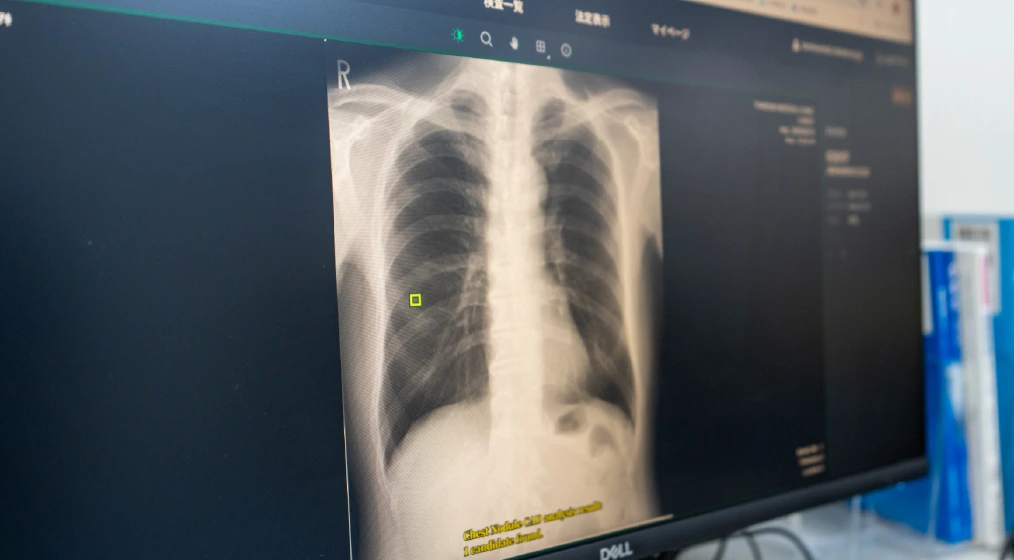

AI技術による精密検査